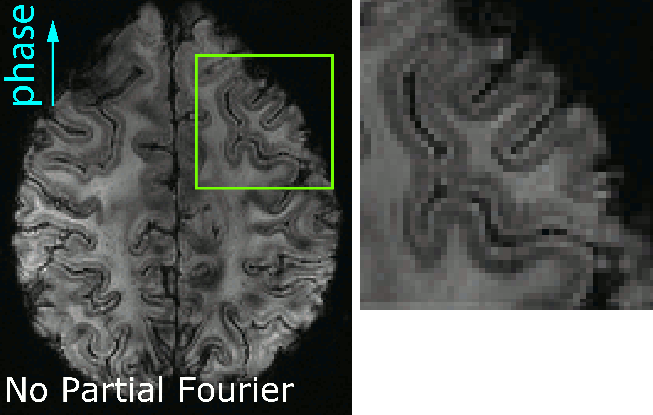

Example 1 of the blurring with and without partial Fourier imaging

I found that that when I was aiming for high-resolutions, it is beneficial to refrain from the application of partial Fourier (PF) imaging as much as possible. For the long readout durations at high-resolutions and the fast T2/T2*-decay at high field strengths results in even stronger blurring of partial-Fourier.